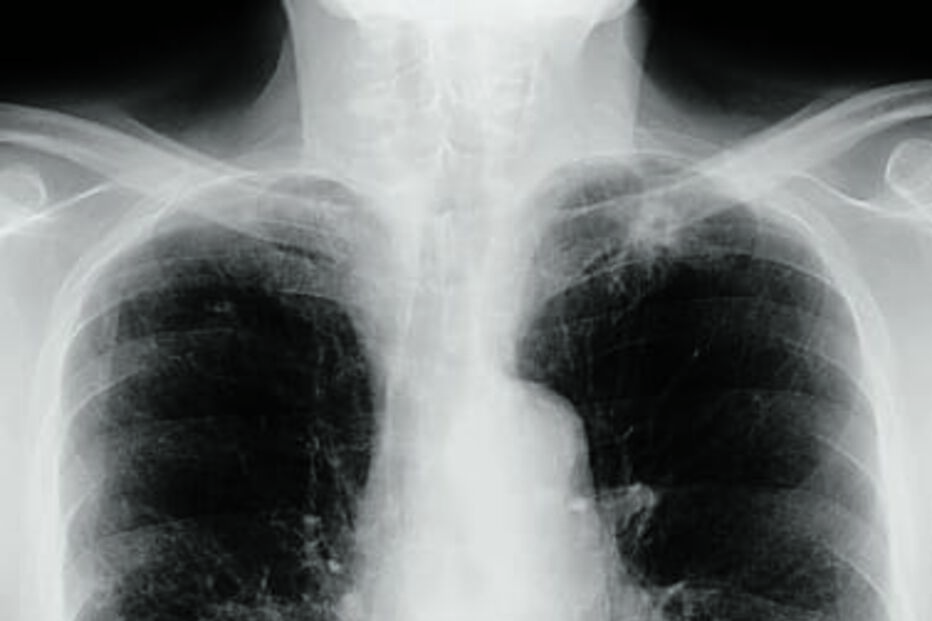

Oito sociedades médicas e outras instituições da área da saúde juntaram-se num documento com recomendações para pressionar a criação de um rastreio nacional ao cancro do pulmão, a neoplasia que mais mata em Portugal, com 4500 mortes anuais.

António Morais, presidente da Sociedade Portuguesa de Pneumologia, sublinha a necessidade de rastreios, para ter um diagnóstico mais rápido, e políticas que apostem na luta contra o tabagismo. "Este duplo caminho é o que temos [de fazer] para efetivamente diminuir este drama relacionado com o cancro do pulmão."